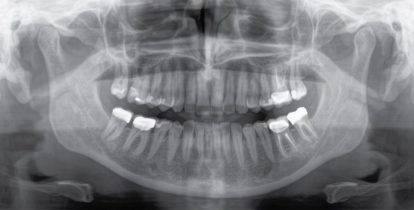

Wysokiej jakości aparat RTG 2D/3D z wszechstronnym zakresem usług dla każdego gabinetu. Czy to jako aparat do obrazowania czysto 2D, czy wraz z modułem 3D – aparat Orthophos S jest solidnym partnerem, zoptymalizowanym do codziennych zadań gabinetu. Dzięki czujnikowi CsI Plus z funkcją autofocus osiągasz za każdym razem wysoką ostrość obrazu nawet w przypadkach trudnych anatomicznie. Opatentowany zagryzak umożliwia automatyczne pozycjonowanie pacjentów. Do zastosowań ortodontycznych Orthophos S wyposażono również w opcjonalne ramię cefalometryczne. Ponieważ gotowość na technologie przyszłości jest priorytetem dla firmy Dentsply Sirona, ramię cefalometryczne i moduł 3D można dołączyć do aparatu w dowolnym momencie.